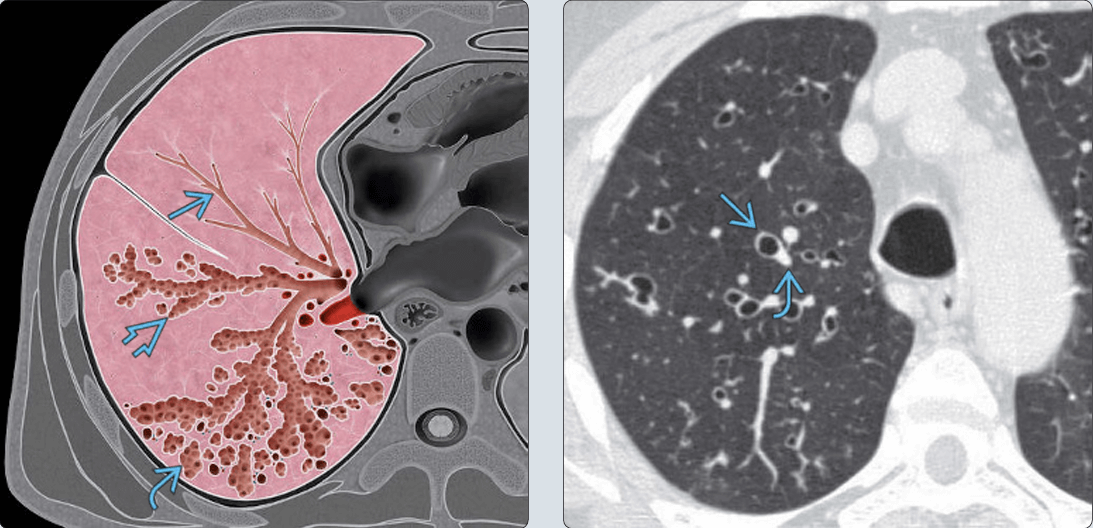

– Giãn phế quản (Bronchiectasis) là giãn không hồi phục một phần của cây phế quản và thường đi kèm với hiện tượng dày thành phế quản và ứ đọng chất nhầy. Có thể giãn ở phế quản lớn trong khi phế quản nhỏ vẫn bình thường hoặc giãn ở phế quản nhỏ trong khi phế quản lớn bình thường.

– Bình thường khẩu kính phế quản ngang với khẩu kính động mạch đi kèm. Trường hợp giãn phế quản, khẩu kính của phế quản sẽ lớn hơn động mạch đi kèm.